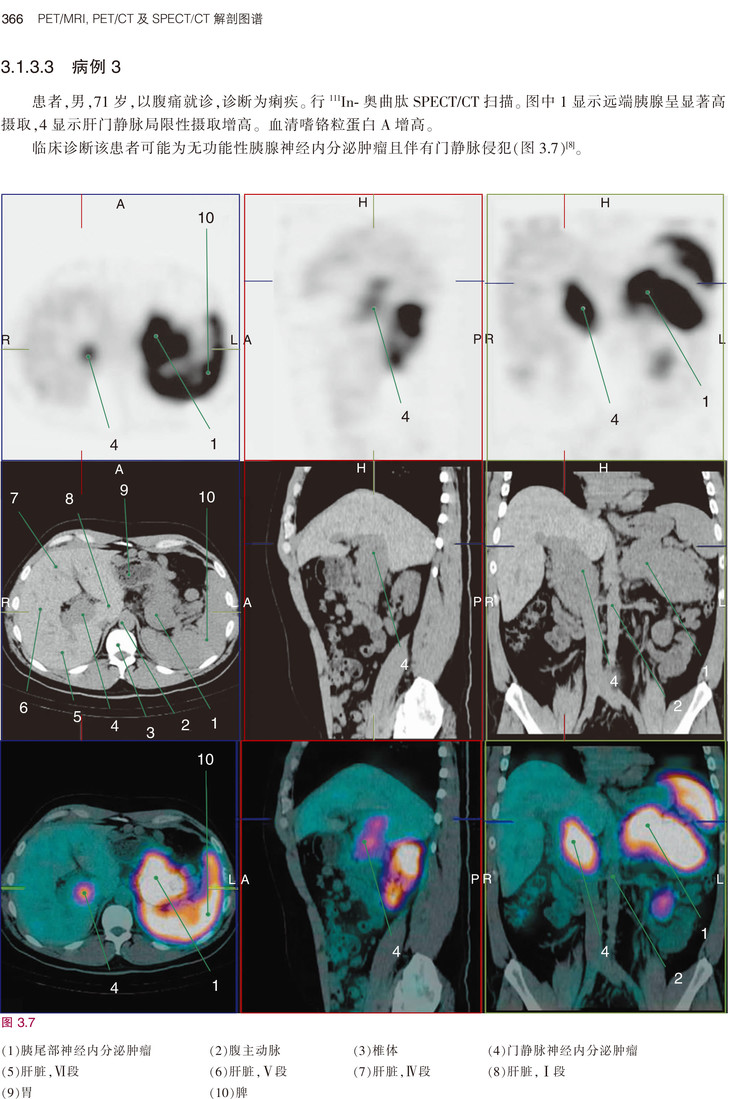

《PET/MRI, PET/CT及SPECT/CT解剖图谱》是目前融合医学影像的经典著作,书中既讲解了基础解剖内容,又有丰富的病例介绍。全书共3章内容,分别为PET/MRI解剖图谱、PET/CT解剖图谱和SPECT/CT解剖图谱。第1章PET/MRI解剖图谱按照大脑、头颈部、胸部、腹部、盆腔、肌肉骨骼系统进行描述。第2章PET/CT解剖图谱按照FDG和非-FDG进行分类描述。第3章则描述了肿瘤、骨和其他病变的SPECT/CT表现。本书编者临床经验丰富、理论基础扎实、科研能力出众,以“融合图像”作为突出特色,荟萃了当今最为先进的PET/CT、PET/MRI及SPECT/CT技术,有助于提升国内从业人员的专业素养、优化诊断思路,进而更好地服务于患者。